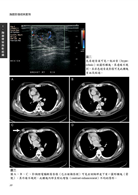

病例18 甲狀腺乳突癌合併氣管侵犯 76

(Tracheal tumor-thyroid papillary carcinoma with trachea invasion)